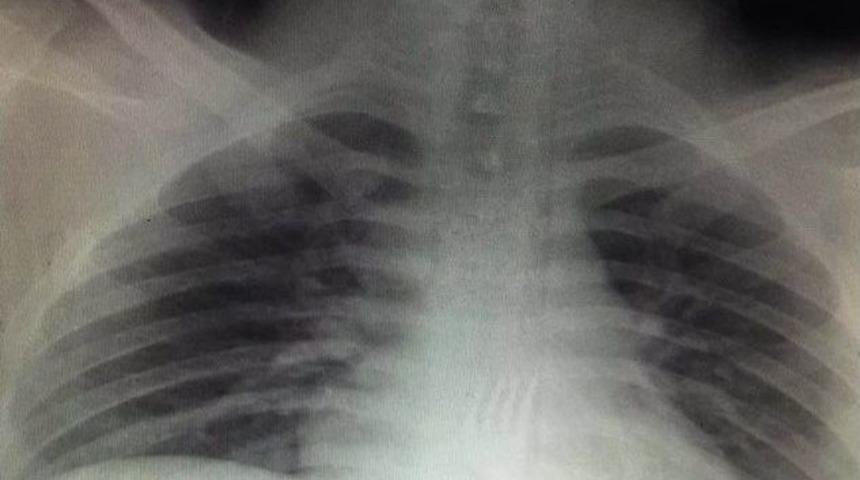

Konya’da zihinsel engelli 20 yaşındaki bir gencin yuttuğu 15 santimetrelik metal çatal, gerçekleştirilen ameliyatla midesinden çıkarıldı.Konya’da yemek yediği sırada 15 santimetre boyundaki metal çatalı yutan 20 yaşındaki O.A., durumu fark eden ailesi tarafından Necmettin Erbakan Üniversitesi Meram Tıp Fakültesi Hastanesi Acil Servise götürüldü. Yapılan tetkikler sonucunda 20 yaşındaki gencin midesindeki çatalın yemek borusunun sonuna kadar inmiş olduğu belirlendi. Bunun üzerine ameliyata alınan O.A.’nın midesindeki çatal, Necmettin Erbakan Üniversitesi Meram Tıp Fakültesi Hastanesi Genel Cerrahi Anabilim Dalı Öğretim Üyesi Prof. Dr. Mehmet Erikoğlu tarafından gerçekleştirilen ameliyatın ardından çıkarıldı.Ameliyatı gerçekleştiren Prof. Dr. Mehmet Erikoğlu, acil servise başvuran hastanın çatal yuttuğunun söylenmesi üzerine gerekli tetkikleri yaptıkların ve ardından hastayı hemen ameliyata aldıklarını söyledi. Erikoğlu, mideden küçük bir kesi ile 15 santimetre boyundaki çatalı bulunduğu yerden çıkardıklarını ifade etti.